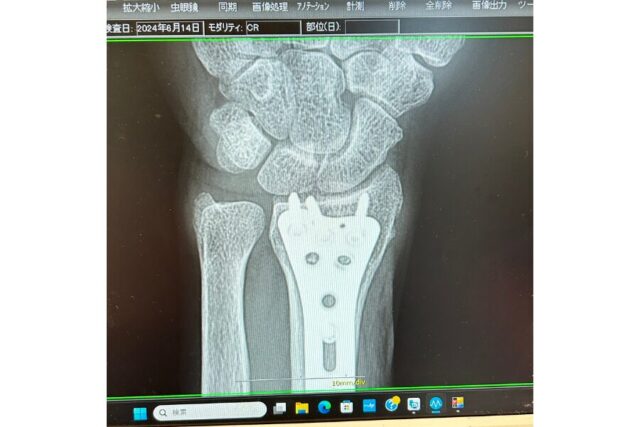

昨シーズン骨折して痛い目にあったのにも関わらず、今シーズン8回も行ったスノボ。

骨が折れた時は痛くて眠れなかったな〜。